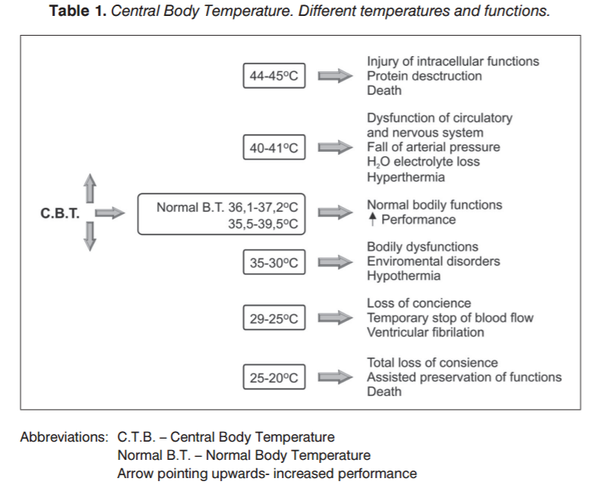

我们人类的核心体温大约是 37℃。

下丘脑作为人体的"恒温器",使我们身体处于一种动态平衡中,即产生的热量和损失的热量相当,从而保持 37℃体温的稳定。

所以,无论气温还是水温,外界温度大于等于 37℃时,我们都是需要借助上述方法散热的。

为了维持核心体温 37℃,外界温度是多少度最合适(无需额外运动,代谢率稳定)?

答案是取决于我们身处的介质——在静止的空气中大约为 21~27℃,在静止的水里大约是 28~33℃。